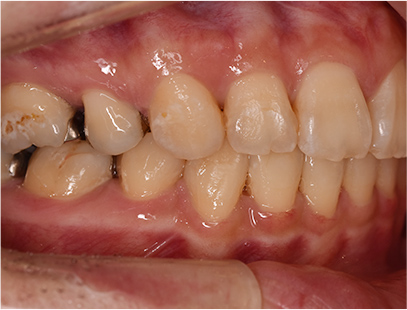

症例03

前歯が出ている症例

上の歯が出いることを主訴として来院されました。

通常通り検査を行い、「上下顎前突」と診断されました。

治療計画

上下4番目の歯を抜歯してそのスペースを利用して上の前歯を内側に移動させる事としました。

治療前

• 矯正治療前の横顔

• 正面

• 上側

• 下側

• 左側

• 右側